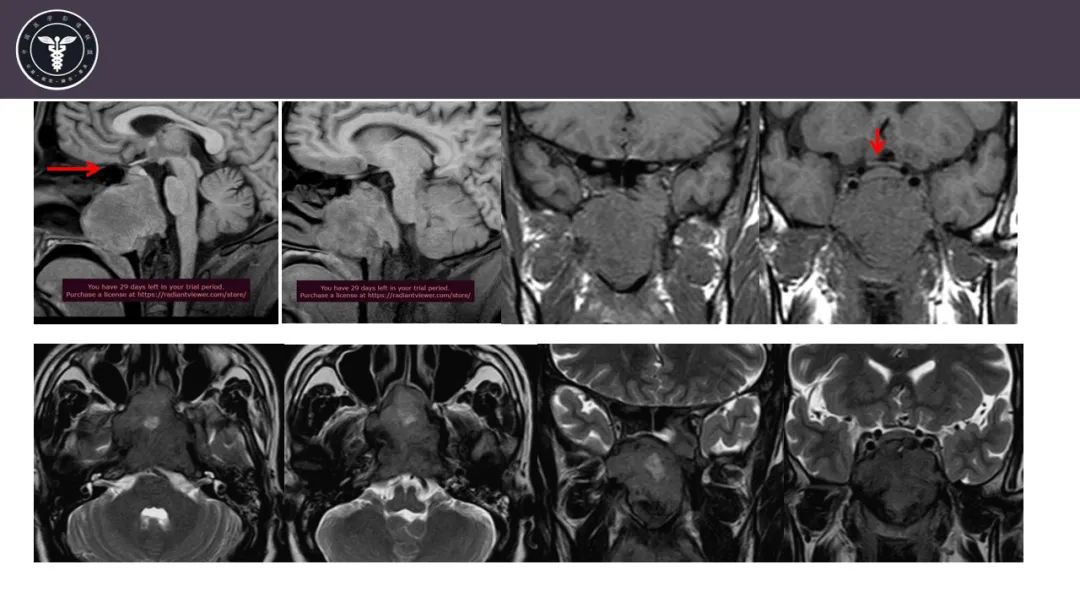

【病例】斜坡区骨巨细胞瘤 VS 脊索瘤-17

【病例】斜坡区骨巨细胞瘤 VS 脊索瘤-18